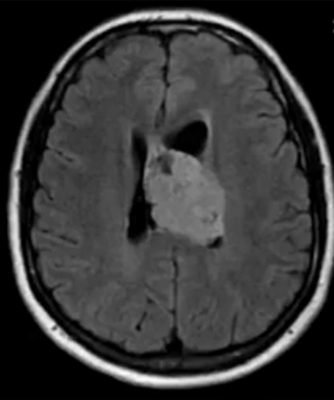

Эпендимома при МР-сканировании головного мозга

- эпендимомы — предположительно образуются в эмбриональном периоде. Характеризуются четкими контурами, плотнее, чем здоровые ткани, редко вызывают отек, чаще обнаруживаются в полостях желудочков;